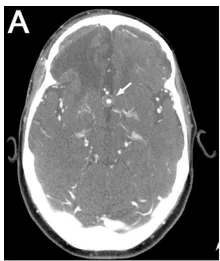

在近期一次癫痫发作及创伤性脑损伤后,患者接受头颅CT及CT血管成像随访检查,结果显示其前交通动脉(ACoA)存在一部分血栓形成及钙化,该动脉瘤原大小为10.3毫米,同时发现右侧脑卒中旧灶。术前CT血管成像显示10.3毫米部分血栓形成的ACoA动脉瘤(箭头指示)。患者对答切题,但存在左侧轻偏瘫及共济失调。